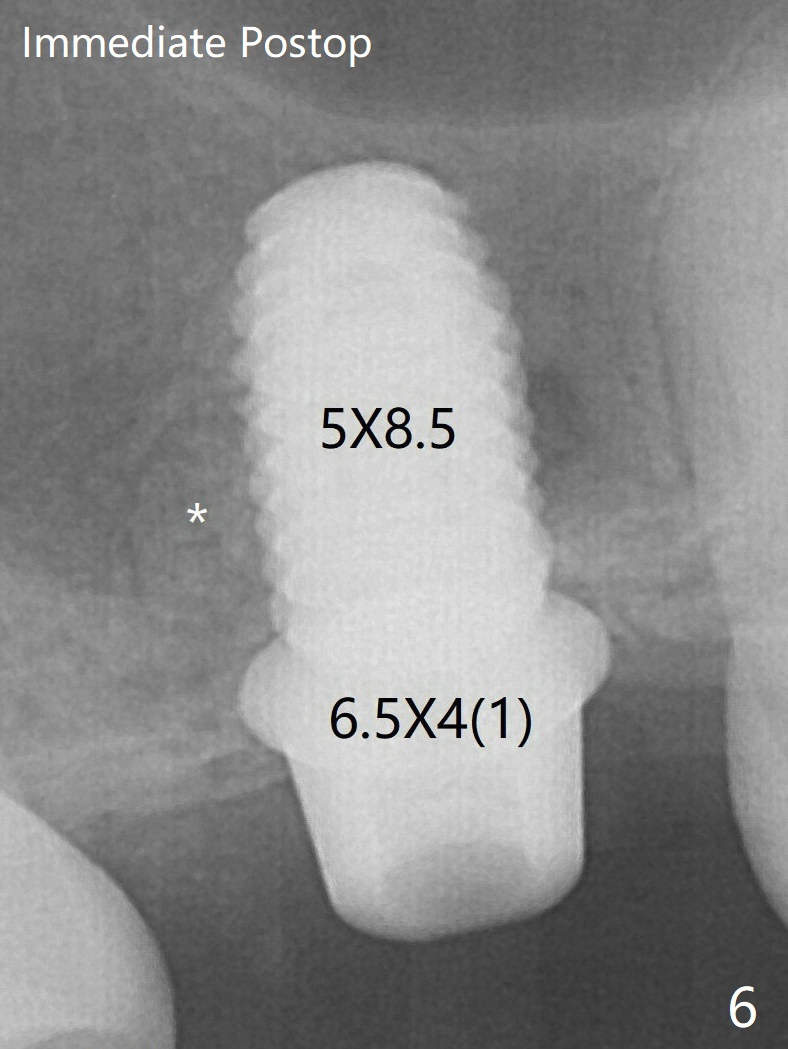

A 4.5x10 mm dummy implant is placed with high torque after 4x7.3 mm drill with 3 mm stopper so that 4.5x7.3 mm drill with 1 mm stopper is used before placement of a 5x8.5 mm final implant with ~ 35 Ncm (Fig.6-7). There is no pain when a 5.2x4(2) mm cemented abutment is torqued at 30-35 Ncm before impression (Fig.8). *: bone graft in the sinus. When the permanent crown is delivered, the patient feels light pain when she bites hard. The discomfort persists 4 months post cementation (Fig.9). The crown/abutment is replaced with a healing abutment (Fig.10).